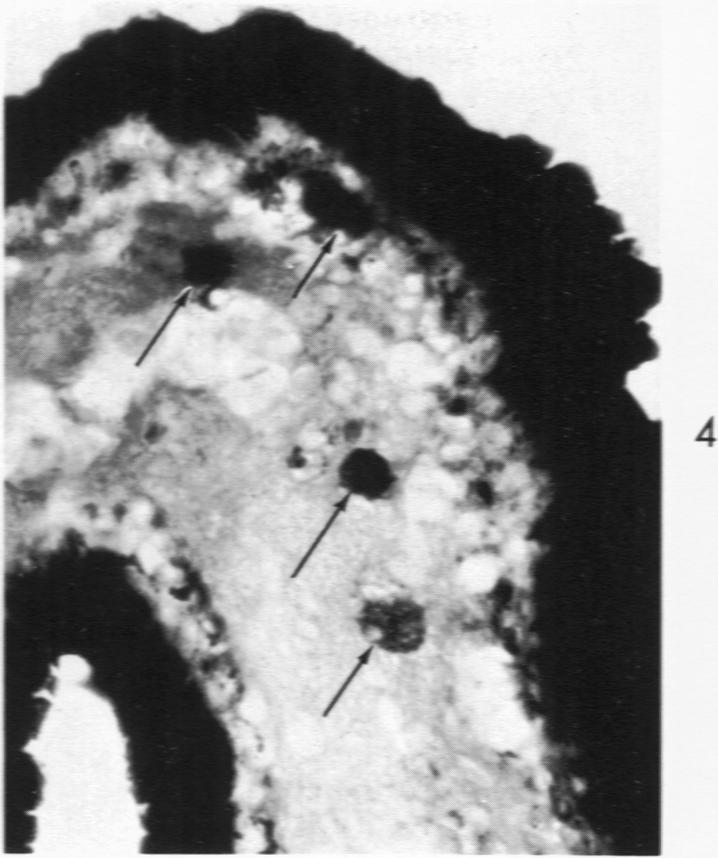

Histochemical and morphologic changes in gastric mucosa of dogs on ulcerogenic regimen.

Am J Pathol. 1969 Jul;56(1):129-51.